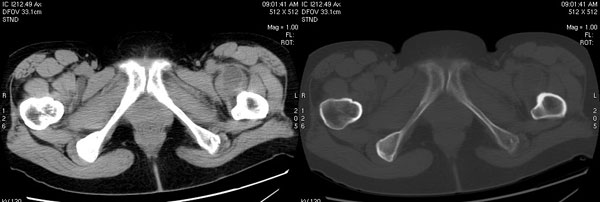

以下是引用jiajie在2006-7-14 17:19:00的发言:[br]ct所见:双侧髋关节不对称,左侧关节间隙变窄,关节面毛糙。左侧股骨头变形、无明显变小,前上缘与髋臼融合,融合处骨质明显增生硬化,并见数个小囊变影。股骨头下端与股骨颈交界部见囊样变,邻近肌肉内见囊样密度减低区,ct值24hu。右侧髋关节形态未见异常。[br][br]ct诊断:左侧髋关节结核可能,请结合临床资料进一步分析。

以下是引用lihuuuu在2006-12-5 10:14:00的发言:[br]定位像示:左侧髋臼变浅,倾斜度加大,髋臼外上缘呈波浪状不规则,骨质增生硬化,髋关节上缘间隙明显变窄,股骨头向外上轻度移位。轴位像示:左侧股骨头变形,前上缘与髋臼融合,融合处骨质明显增生硬化,并见数个小囊变影。股骨头下端与股骨颈交界部见囊样变,邻近肌肉内见密度减低区,ct值24hu,内缘见弧形高密度钙化影。右侧髋关节形态未见异常。[br]ct诊断:左侧髋臼发育不良[br] 左侧股骨头缺血性坏死[br] 左侧肌肉内低密度影伴有高密度钙化-考虑早期骨化性肌炎[br] [br]“我认为在描述上已经写了肌肉部分,印象诊断里应该写主见”[br]